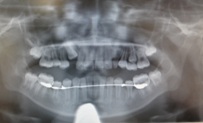

レントゲンを撮影して永久歯が思わぬ方向を向いている場合があります。

そんな場合には乳歯を早く抜歯して、永久歯の萌出を促し、永久歯の生えてくる

スペースを保つ必要があることもあります。

以下は、当院での症例です。